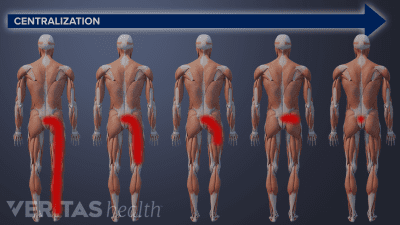

McKenzie therapy is not advised for treating pain from serious back or neck injuries, after spine surgery, or in cases where the pain does not centralize.

You may experience significant pain relief after just one session of McKenzie exercises, but it takes at least 1 to 3 weeks of therapy to get sustained pain relief.